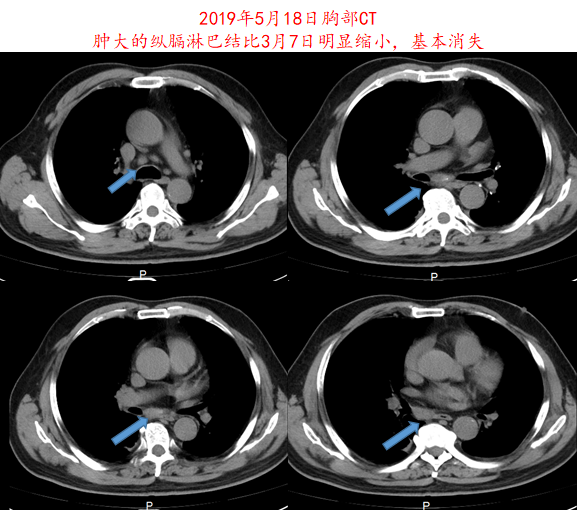

2019年4月16日开始给予信迪利单抗(200mg,q3w)+阿帕替尼(250mg,qd)治疗,治疗1周期后,患者症状明显改善,2周期后复查CT,疗效评价为部分缓解(PR;图3-4)。治疗期间患者出现1-2级皮疹,未观察到其他副作用。

image005.png

image006.png

图4.患者2019年5月18日胸部CT影像资料